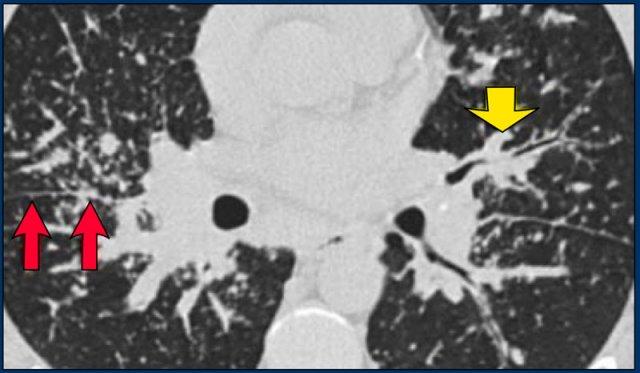

Hình ảnh điển hình của sarcoidosis với hạch to rốn phổi và các nốt nhỏ dọc theo bó mạch phế quản (mũi tên vàng) và dọc theo các khe liên thùy (mũi tên đỏ).

Hình ảnh chi tiết với biểu hiện HRCT điển hình gồm các nốt dọc theo bó mạch phế quản (mũi tên đỏ) và các khe liên thùy (mũi tên vàng).

Đây là phân bố theo đường bạch huyết điển hình của các nốt.